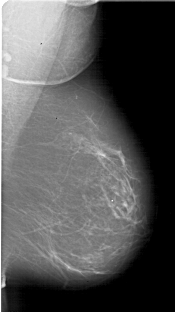

A_1778_1.RIGHT_MLO

RIGHT_MLO LINES 5911 PIXELS_PER_LINE 3316 BITS_PER_PIXEL 12 RESOLUTION 43.5 NON_OVERLAY